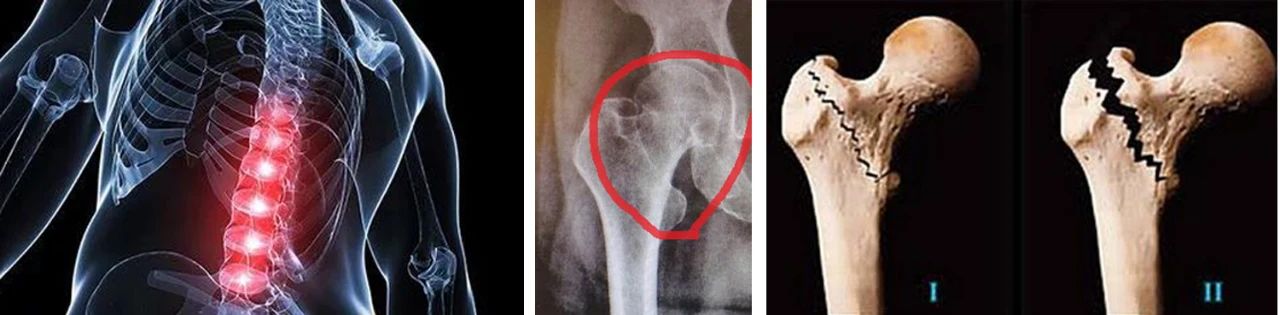

老年人摔倒时,有三大部位最容易发生骨折,分别是腰椎压缩性骨折、髋部骨折(股骨颈或转子间骨折)和桡骨远端骨折。

河北省老年病蜜桃视频 骨一科针对老年人跌倒所致的脊柱压缩骨折,老年四肢骨折,以及常发的老年髋部骨折等,应用微创、手术、固定等多种方法,帮助老年患者快速康复,最大程度提高老年患者生活质量。